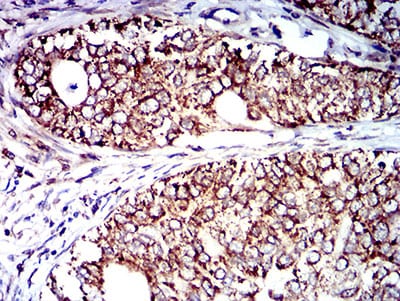

分类: 科研抗体货号: 31428别名: IN; LHR; MC56; MDU2; MDU3; MIC4; Pgp1; CDW44; CSPG8; HCELL; HUTCH-I; ECMR-III应用: WB,IHC,FCM反应种属: Human

分类: 科研抗体货号: 31412别名: IL9R; IL-9R应用: WB,IHC,FCM反应种属: Human,Rat

分类: 科研抗体货号: 31397别名: FBP; FOLR应用: IHC,IF,FCM反应种属: Human

分类: 科研抗体货号: 31427别名: IN; LHR; MC56; MDU2; MDU3; MIC4; Pgp1; CDW44; CSPG8; HCELL; HUTCH-I; ECMR-III应用: WB,IHC,FCM反应种属: Human